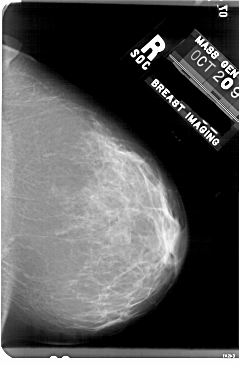

A_1758_1.RIGHT_CC

RIGHT_CC LINES 5476 PIXELS_PER_LINE 3571 BITS_PER_PIXEL 12 RESOLUTION 43.5 NON_OVERLAY